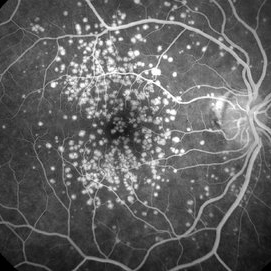

Proliferative Diabetic Retinopathy

Male patient, 16-years-old, with type II diabetes mellitus, 320 MD / DL mean of glycemic control of the last five months. He attended the clinic complaining of low vision of both eyes. In the fluorescent retinal examination, several extravasation points corresponding to retinal neovascularization (Proliferative Diabetic Retinopathy) were observed.

Photographer: JEFFERSON R SOUSA - Study Center and Ophthalmological Research Dr. Andre M V Gomes, Dr. Suel Abujamra Institute São Paulo-Brazil

Imaging device: Acquisition of the image in the Camera background Topcon TRC-50 Dx - IA, Keystone field photo of 50 Degrees. Composition automatic of Imaginet with manual adjustment.

Condition/keywords: proliferative diabetic retinopathy (PDR)